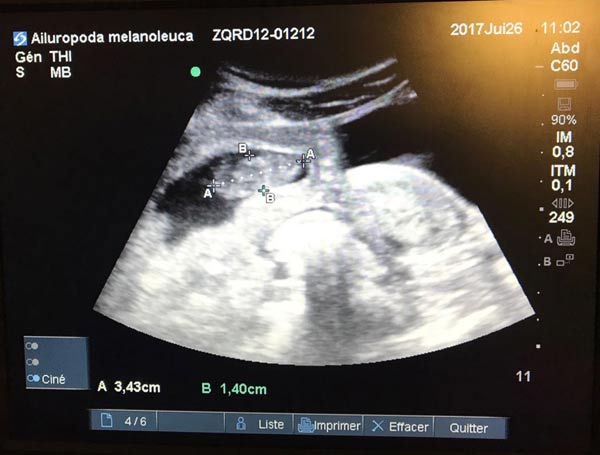

Chinese panda Huan Huan, which is on loan to France, is expecting twin cubs, according to the zoo which carried out a medical examination and revealed the results exclusively to China Daily on Tuesday. [Photo provided to China Daily]